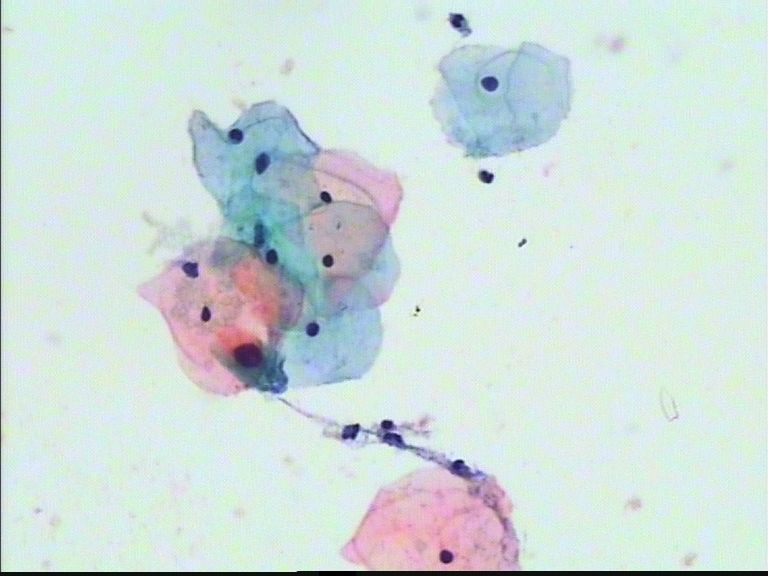

跟法律一样,关键在证据.证据有时也不一定就是真实的,因此会有冤假错案出现.排除人为因素,几乎每一个有良知的法律工作者都希望办成一个铁案,经得起历史检验.但,事实上,这是一种最高理想.

细胞学亦如此.

无论CIN2,3,原位癌,在细胞学上都应有其证据.如果没有,不能想当然猜测,虽然报的结果可能与实际不符,但原因也许不是单一的.在力求达到"真实"的同时,也要规避风险.作为筛查方法,够了.

本例的细胞看不出CIN3,LSIL是可以的,也许有倾向于CIN2的可能,但不能直接诊断HSIL.原因找不到确切的,因为原因不是单一的.比如取材\病变局限\制片.................